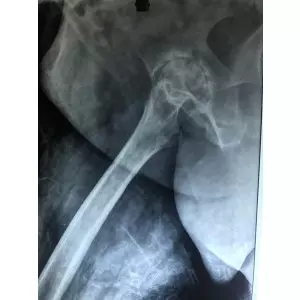

Dr Samir Nanavati